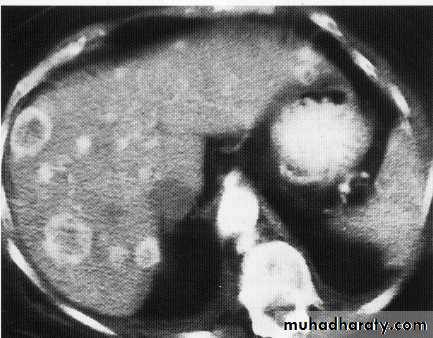

hepatic mets

hepatic mets,arterial phase

hepatic mets venous phase